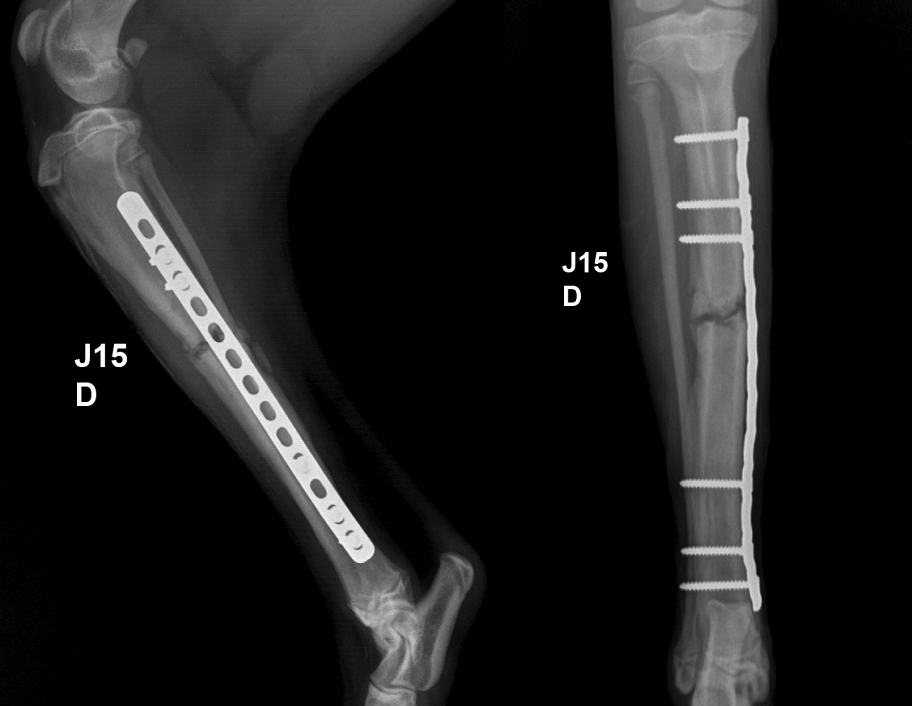

Web L'ostéosynthèse Est Une Opération Chirurgicale Qui Consiste À Maintenir Entre Eux Les Fragments D'un Os Cassé, Grâce À Des Matériaux Métalliques Tolérés Par L'organisme Et.

Elle est réservée aux fractures complexes, qui ne. Web ostéosynthèse avec plaque, avantages et inconvénients l’ostéosynthèse permet une période de décalcification plus courte et une. Web l’ostéosynthèse est réservée aux fractures complexes, qui ne peuvent être réduites par des moyens simples extérieurs tels qu’un plâtre.

Web Ostéosynthèse L'ostéosynthèseregroupe L'ensemble Des Procédés Qui Permettent De Traiter Des Fractures Ou Des Problèmes D'ordre Mécanique Sur Le Squelette À L'aide De Vis, De.

Les plus répandues (grande disponibilité des plaques et des vis). Web inconvénients de l’ostéosynthèse ? Dans les années 1960, muller et allgöwer ont établi les.